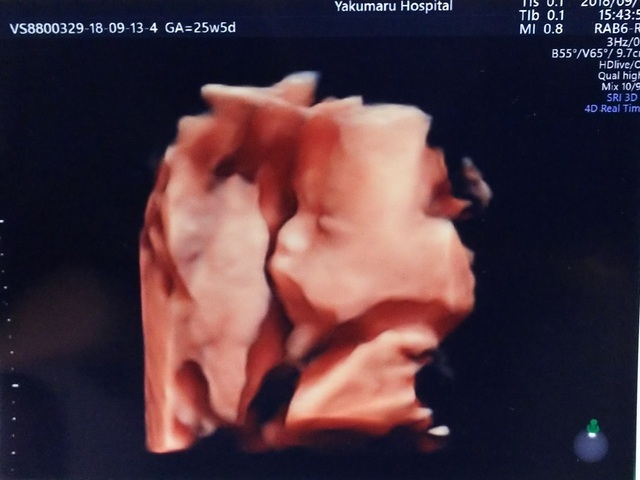

25週0日(25w0d・男の子)|ち75 さん(32歳)

エコー写真撮影時のエピソード:

昔にバンドのボーカルをやっていたり、歌うことも音楽を聴くことも好きなので、妊娠中は今まで行こうと思って行けなかったバンドのライブに行く事にしました。

ライブ中も胎動が激しい曲や何も動かない曲など、好みがあるみたいで面白かったです。エコー写真は歌っている様に、口をパクパクしていた時の息子です。